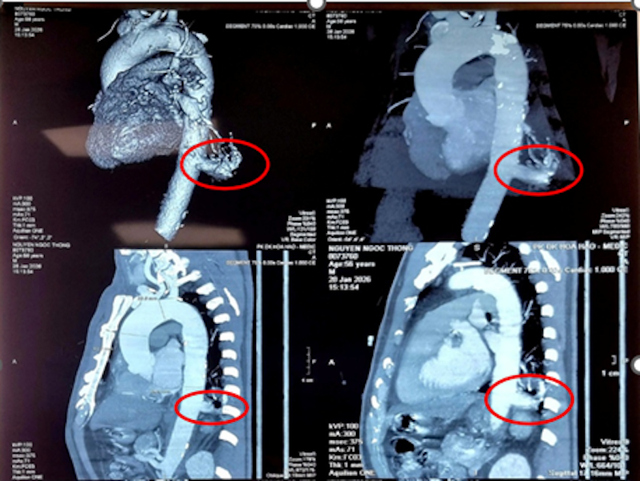

Tổn thương của bệnh nhân có kích thước 23 x 26mm, được nuôi bởi một nhánh động mạch xuất phát trực tiếp từ động mạch chủ xuống, đường kính tới 17mm. Theo ThS.BSCKII Nguyễn Văn Việt Thành, Trưởng khoa Ngoại Lồng ngực – Bướu cổ, khó khăn lớn nhất là xử lý mạch máu lớn, thành mạch dễ vỡ và dính do viêm mạn tính; chỉ một sai sót nhỏ có thể gây chảy máu nghiêm trọng.

Hình chụp tình trạng ngực của bệnh nhân.

Sau hội chẩn toàn viện, ê-kíp quyết định lựa chọn phẫu thuật robot để tối ưu độ chính xác và an toàn. Công nghệ này cung cấp hình ảnh 3D phóng đại rõ nét, cánh tay linh hoạt và loại bỏ rung tay tự nhiên, hỗ trợ bóc tách, kiểm soát mạch máu sát động mạch chủ tinh vi hơn.